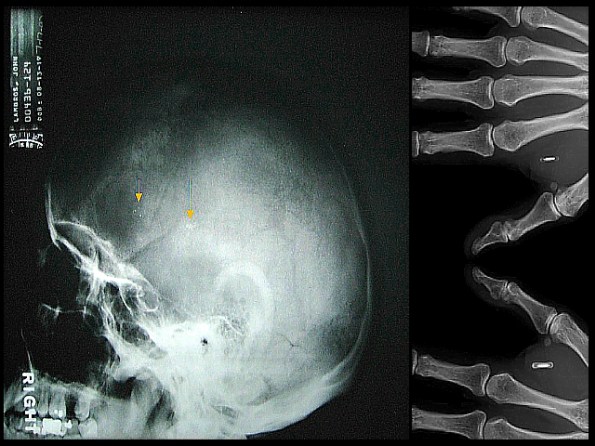

VeriChip is the only Food and Drug Administration (FDA)-approved human-implantable radio-frequency identification (RFID) microchip. It is marketed by PositiveID, a subsidiary of Applied Digital Solutions, and it received United States FDA approval in 2004. About twice the length of a dime, the device is typically implanted between the shoulder and elbow area of an individual’s right arm.[1] Once scanned at the proper frequency, the VeriChip responds with a unique 16 digit number which could be then linked with information about the user held on a database for identity verification, medical records access and other uses. The insertion procedure is performed under local anesthetic in a physician’s office. As an implanted device used for identification by a third party, it has generated controversy and debate. Destron Fearing, a subsidiary of Applied Digital Solutions, initially developed the technology for the VeriChip. According to Wired News online, and the Associated Press, there have been research articles over the last ten years that found a connection between the chips and possible cancer. When mice and rats were injected with glass-encapsulated RFID transponders, like those made by VeriChip, they “developed malignant, fast-growing, lethal cancers in up to 1% to 10% of cases” at the site at which the microchip was injected or to which it had migrated. However, the 10% rate was obtained with hemizygous p53-deficient mice, the counterpart of humans with the Li-Fraumeni syndrome, and rates near 1% were more typical. The Verichip corporation responded to this report, which caused a 40% drop in their stock value, by stating that rodent data had been provided to the FDA and did not reflect the effect of the chips in humans or pets. Dogs, alternatively, are more resistant to the formation of malignant soft tissue tumors in response to foreign body insult. Induction of sarcomas by foreign bodies has been reported in humans, and has been described as analogous to rodent foreign body-associated sarcomas and is fairly infrequent. Resolution of the question may be hindered by the long delay in onset of sarcoma induction or other deleterious side effects, analogous to the controversy in the mid 20th century over asbestos exposure and predisposition to mesothelioma. Tommy Thompson, the former Secretary of Health and Human Services, supports the VeriChip as a “useful tool in sharing medical information with health care providers in emergency situations”. Thompson also sits on the board of directors of VeriChip’s parent company Applied Digital Solutions. In June 2007, the American Medical Association declared that “implantable radio frequency identification (RFID) devices may help to identify patients, thereby improving the safety and efficiency of patient care, and may be used to enable secure access to patient clinical information” (Wikepedia).